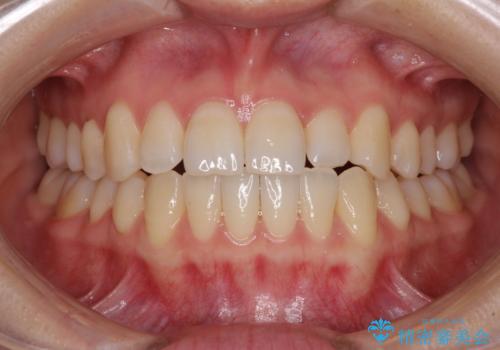

前歯のクロスバイト インビザラインによる矯正治療

- 前歯のクロスバイトを気にして来院された患者様です。

短期間での治療を希望され、ワイヤー装置とインビザラインとで悩んでいましたが、自己管理を徹底すると言うことでインビザラインによる矯正治療を行うこととしました。

しっかりとインビザラインの装着時間を守っていただいたので、1年弱で矯正治療を終えることができました。